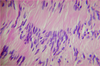

A 74 year old man with long-standing HTN who refused to take any medications or change his lifestyle comes to the ED after collapsing in his home. He is unresponsive and demonstrates R-sided paralysis and eventually expires. At autopsy there are signs of massive hemorrhage within the thalamus and the following histologic changes are found. What is his diagnosis?

Hypertensive Hemorrhage

Rupture of a cerebral blood vessel as a consequence of long standing hypertension

The most common locations for hypertensive cerebral hemorrhages are:

- the basal ganglia and thalamus (65%),

- the pons (15%)

- the cerebellum (8%).

May be related to lipohyalinosis of small vessel walls–> formation of microscopic Charcot-Bouchard aneurysms

Hemorrhage in the region of the internal capsule causes paralysis of the opposite side of the body.

- Patients are usually however unconscious

An acute hemorrhage in the pons may damage cranial nerve nuclei or result in loss of consciousness due to damage to reticular formation.

A cerebellar hemorrhage may cause abrupt ataxia, severe occipital headache and vomiting and may cause life-threatening compression of medulla.

- *Histo:** hypertensive arteriosclerosis in patient with long-standing HTN

- front: Charcot-bouchard aneurysms (mural deposition of lipid, hyaline–> damage to cerebral arterioles)